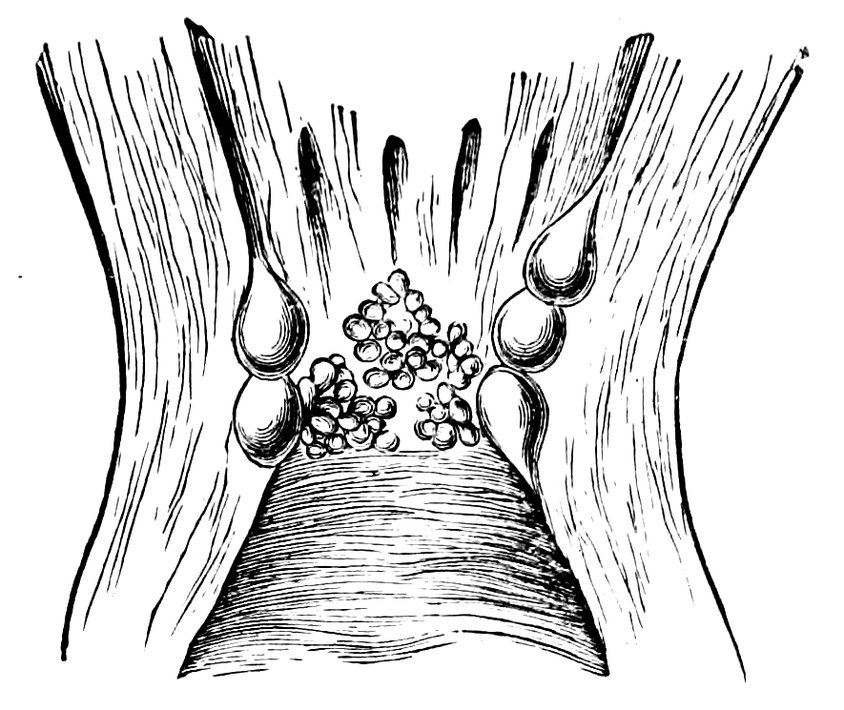

| 15. | Primitive follicles | 58 |